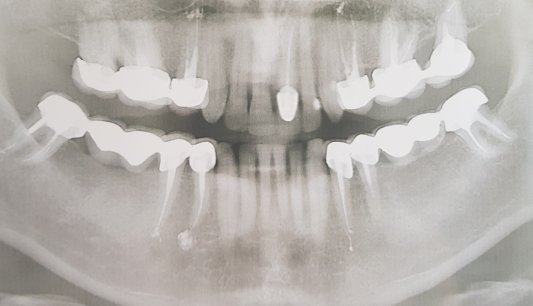

Что делать, подскажите пожалуйста? (1й снимок после первого лечения, 2-й после перелечивания)

Канал зуба на первом снимке запломбирован хорошо, я не вижу там резорцин-формалина, так как он на рентгене контрастен, а на снимке явно видна пломбировка силлером. Боли не понятно с чем связаны. Зачем нужно было выводить материал за верхушку? Это грубое нарушение!

Я предполагаю, что проблема может быть связана с дополнительным ответвлением. Обратитесь в клинику к более опытному терапевту с навыками работы с микроскопом.